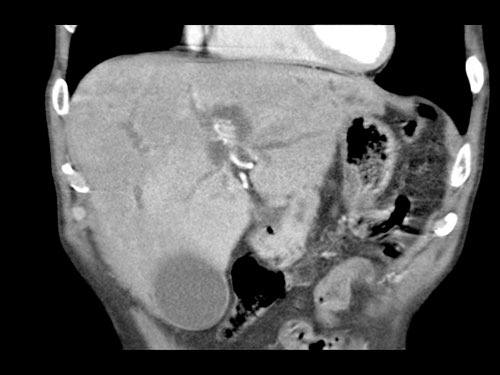

CT axial (a) trước điều trị tân bổ trợ cho thấy khối u ở mặt trong đầu tụy (đầu mũi tên), không thể cắt bỏ do xâm lấn thần kinh lan rộng với mức độ bao quanh 360 độ động mạch mạc treo tràng trên (SMA) (mũi tên trong b, tái tạo mặt phẳng coronal).

CT theo dõi sau 8 chu kỳ FOLFIRINOX (c,d) cho thấy bệnh ổn định với tình trạng bao quanh SMA vẫn còn tồn tại. Khối u được đánh giá có thể cắt bỏ trong quá trình phẫu thuật nội soi thăm dò. Kết quả giải phẫu bệnh: T3bN2R0.